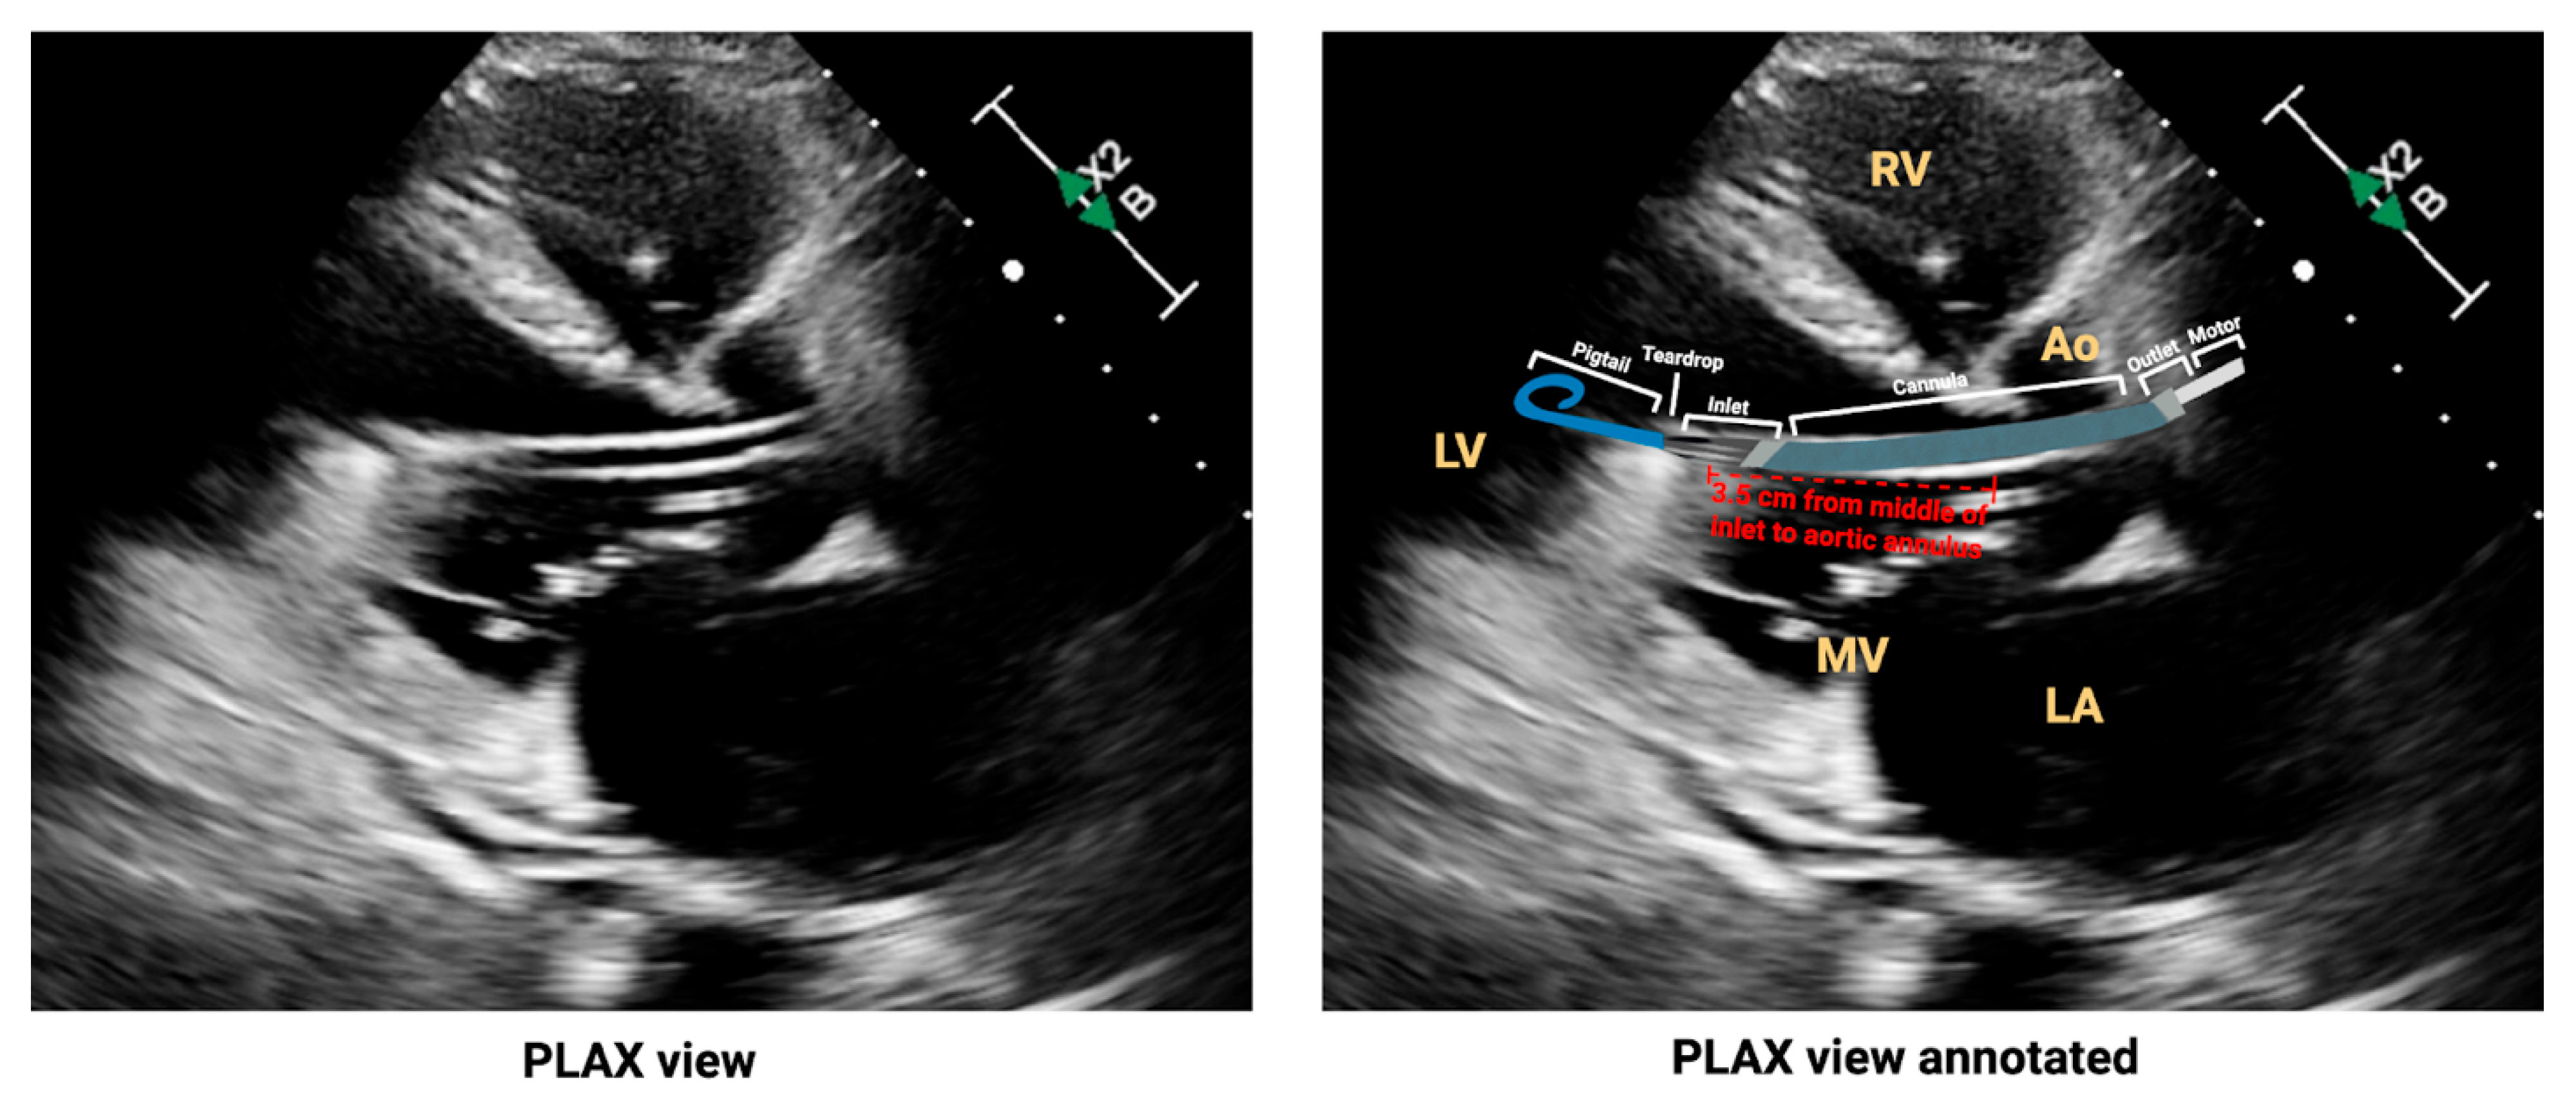

- Tran, T.; Mudigonda, P.; Mahr, C.; Kirkpatrick, J. Echocardiographic imaging of temporary percutaneous mechanical circulatory support devices. J. Echocardiogr. 2022, 20, 77–86. [Google Scholar] [CrossRef]

- Sacks, S.; Feinman, J. A 2024 Update From the American Society of Echocardiography: Multimodality Imaging for Patients With Left Ventricular Assist Devices and Temporary Mechanical Circulatory Support. J. Cardiothorac. Vasc. Anesth. 2025, 39, 1919–1923. [Google Scholar] [CrossRef]

- Burzotta, F.; Trani, C.; Doshi, S.N.; Townend, J.; van Geuns, R.J.; Hunziker, P.; Schieffer, B.; Karatolios, K.; Moller, J.E.; Ribichini, F.L.; et al. Impella ventricular support in clinical practice: Collaborative viewpoint from a European expert user group. Int. J. Cardiol. 2015, 201, 684–691. [Google Scholar] [CrossRef]

- Baldetti, L.; Beneduce, A.; Chieffo, A.; Scandroglio, A.M. Technical tips for inserting and positioning the Impella device. Card. Interv. Today 2023, 17, 60–65. [Google Scholar]

- Catena, E.; Milazzo, F.; Paino, R.; Pittella, G.; Garatti, A.; Colombo, T.; Mantero, A.; Vitali, E.; Merli, M. Transesophageal and transthoracic echocardiography in the monitoring of a new endovascular left ventricle assist device. Ital. Heart J. Suppl. 2003, 4, 428–432. [Google Scholar] [PubMed]